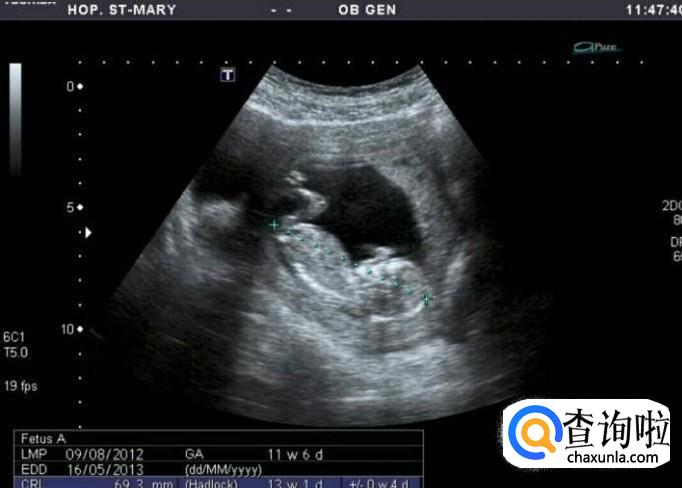

看长宽相差

长和宽的相差在一倍以上男宝宝的可能性大,长和宽相等女宝宝可能性大

看形状差异

像茄子或长条状的是男宝宝可能性大,圆圆的是女宝宝可能性大

B超数据不能超过8周,40多天是最合适的,最好要有3个数据。

如果孕囊成等差数列,比如40*30*20,这样就是女孩。而两个数据差不多,第三个数据比前两个小一倍,那就是男孩。